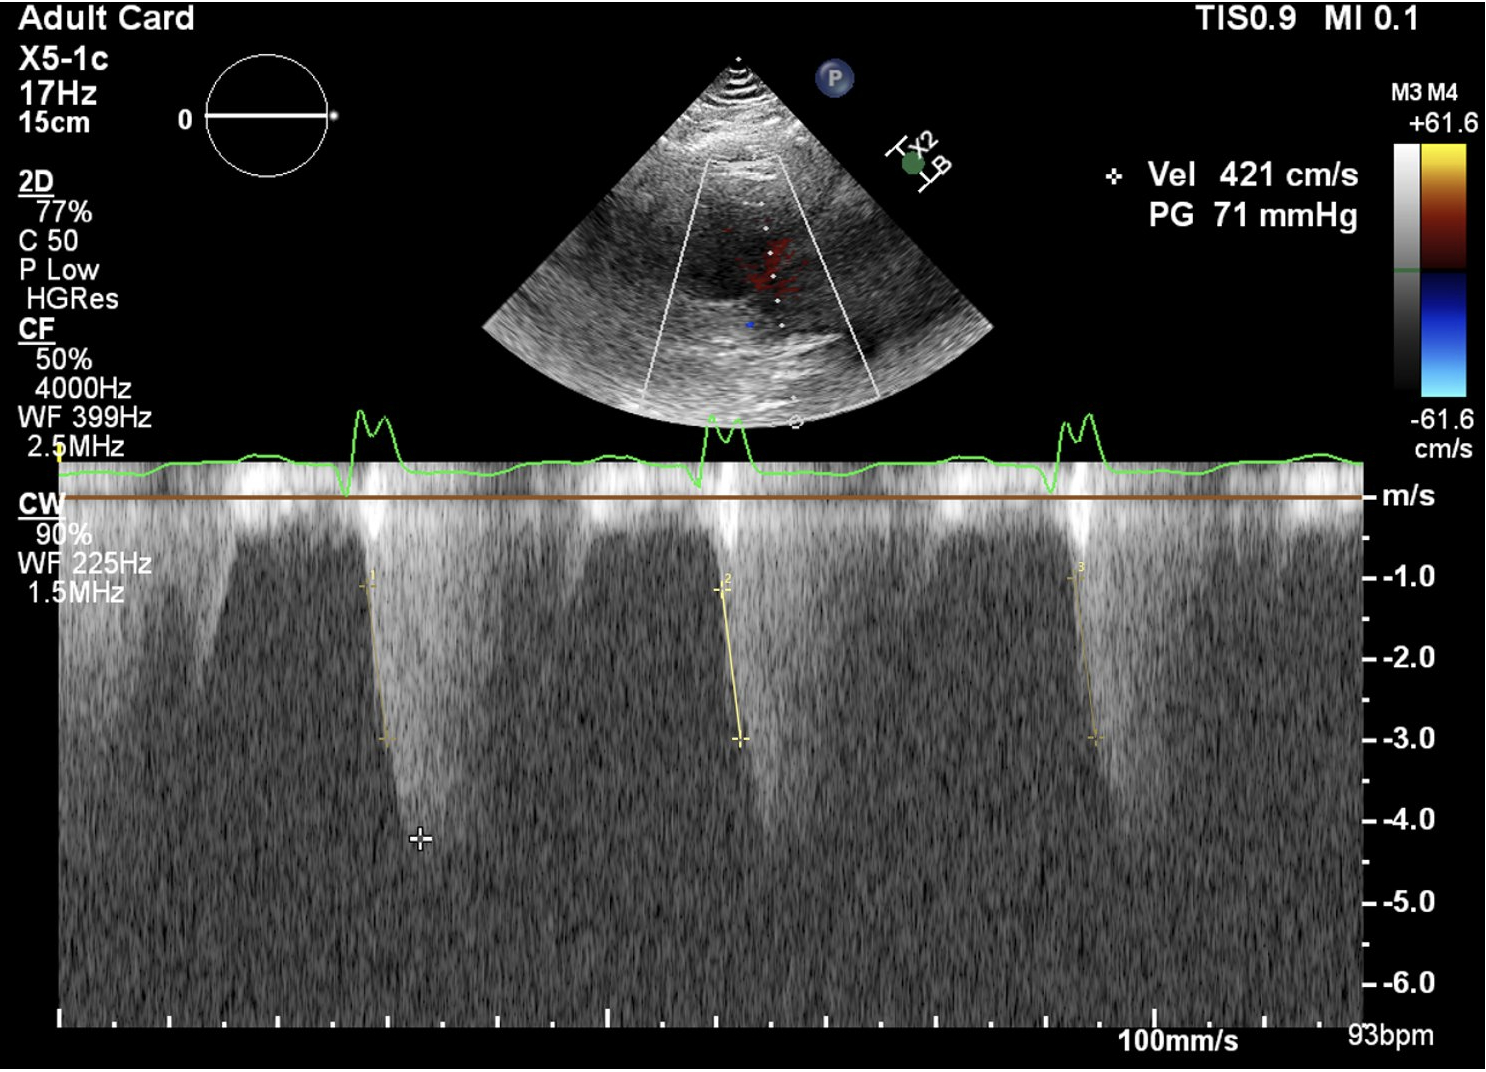

Staged palliation process for single ventricle (SV) patients alters preload, afterload, and ventricular mechanics, making accurate function assessment essential. Left ventricular echocardiography markers have been applied to SV patients such as ejection fraction (EF), though reliability is limited. Continuous wave Doppler (CWD)-derived dp/dt during isovolumetric contraction has surfaced as a potential non-geometric contractility index.

This was a single-center retrospective study of SV patients ≥18 at the Ahmanson/UCLA between 2010-2024. Inclusion required echo and CMR with volumetrics within one year. We measured dp/dt by obtaining the time interval that AV regurgitation velocity increased from 1 to 3 m/s. Correlation, linear regression, and ROC analysis were performed.